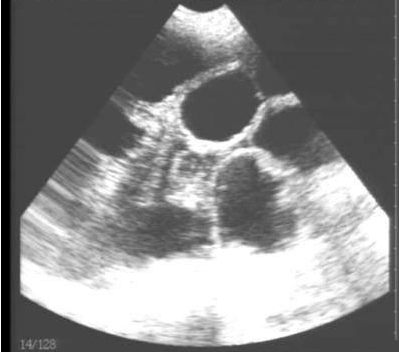

豬用B超機檢測有胎兒圖像

需要注意的是,出現(xiàn)云團狀必須雙側(cè)檢查加以確認.根據(jù)B超機顯示圖我們大致可以判斷孕齡.圖像呈橢圓或者卵圓形大致為30天左右孕齡;圖像呈橢圓形或者卵圓形外,有明顯發(fā)亮骨骼圖像大致為50孕齡左右;圖像囊胚消失,發(fā)亮處隱約可見竹節(jié)狀東西為成型胎兒骨骼,一般為后期80孕齡以后。一般B超機成像會出現(xiàn)三種顏色,白色、黑色、灰色。白色為密度較高的物體,如骨骼或者結(jié)實.黑色一般為液體,包括血液、羊水、組織間隙液體、炎癥病灶等。灰色一般為實質(zhì)性物質(zhì),如肌肉。